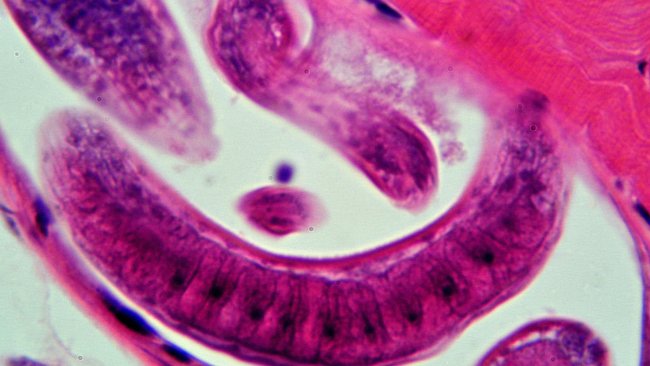

Ausencia de infección por Trichinella en cerdos comerciales en EE.UU.

Una investigación del USDA documenta la ausencia de infección por Trichinella en cerdos comerciales.